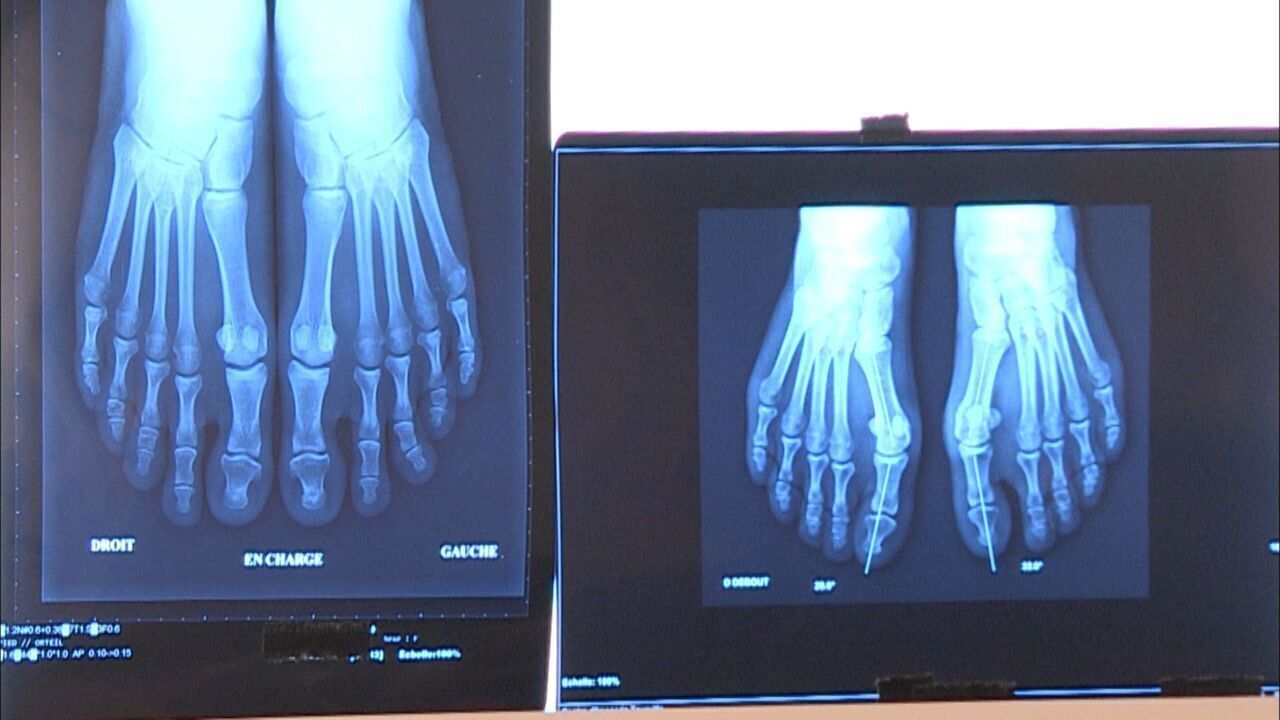

Težave s stopali, ki jih ni več mogoče prezreti: kdaj je čas za operacijo?